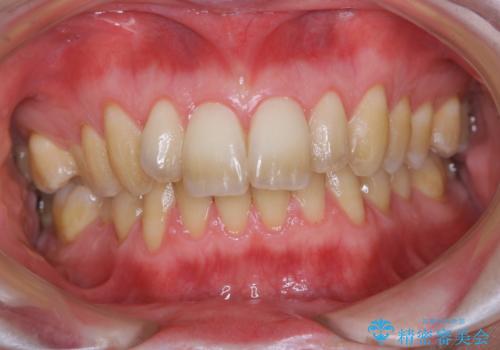

- かなり久しぶりの来院とのことで、クリーニング希望でした。全体的に汚れの付着があったため、PMTCの60分コースを行いました。